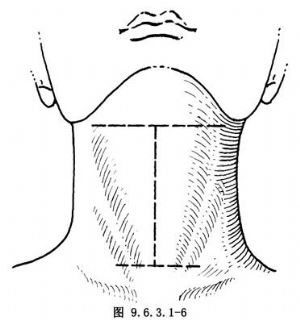

橫I形切口,在T形切口的基礎上將舌骨平面之橫切口沿下頜下緣向兩側延長達乳突尖。另一切口在縱切口下端,橫切開達兩側胸鎖乳突肌的外後緣(圖9.6.3.1-6),此切口適於行喉全切除術並雙頸淋巴結清掃術。